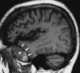

Temporal lobe hematoma

Intracerebral hemorrhage (ICH), also known as cerebral bleed and intraparenchymal bleed, is a sudden bleeding into the tissues of the brain, into its ventricles, or into both. It is one kind of bleeding within the skull and is one kind of stroke.Symptoms can include headache, one-sided weakness, vomiting, seizures, decreased level of consciousness, and neck stiffness. [Source: Wikipedia ]